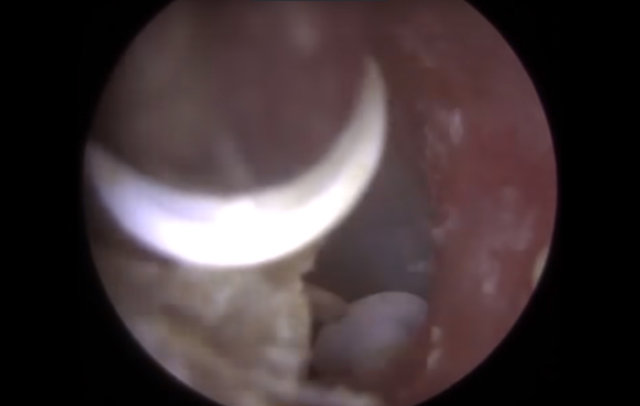

Kulağından 22 tane nesne çıkarılan adam hayrete düşürdü. İşin garip yanı ise kulağının içinden çıkan şeylerin işitme cihazı olmasıydı...